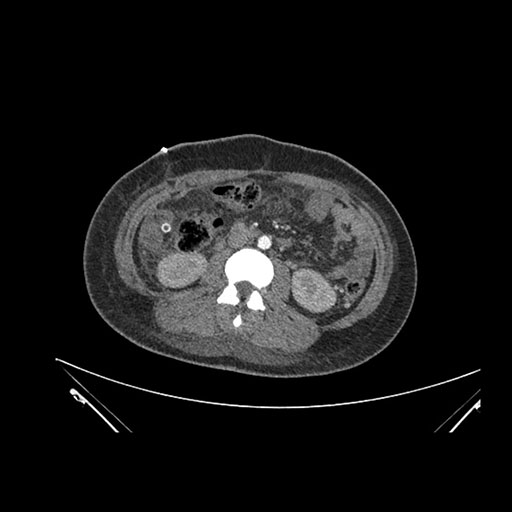

Imaging Analysis

Look through the patient's CT scan to identify any areas of concern for the necessary procedure.

Axial Arterial

Based on initial findings, which issue(s) would you be most concerned about?